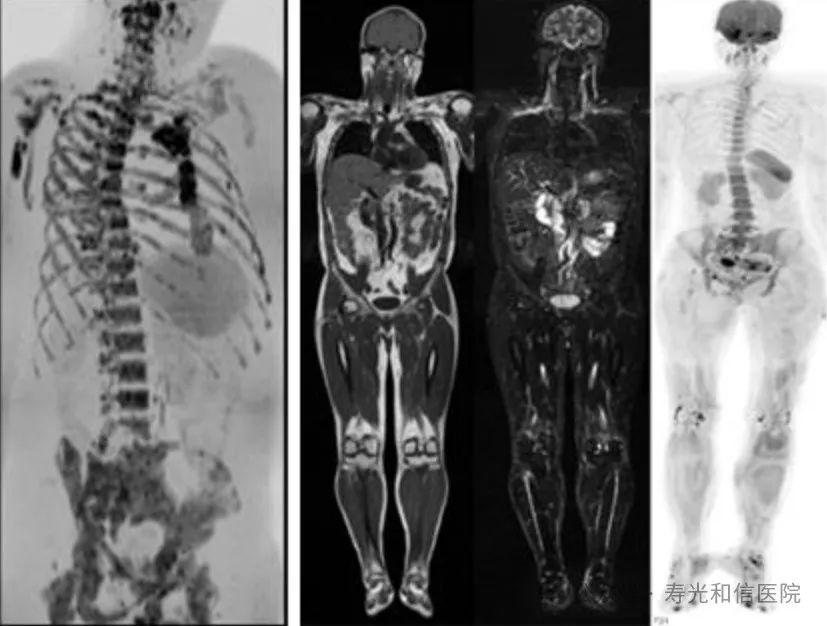

直接冠状位全身类 PET 成像

在全身弥散加权成像的同时,可进行磁共振全身扫描,增加肿瘤检出敏感性。

临床应用范围:寻找恶性肿瘤原发灶;恶性肿瘤分期;全身转移灶筛查;淋巴结转移筛查;术后放化疗疗效监测;恶性血液肿瘤疗效观察;体检与肿瘤筛查。